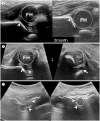

Developmental dysplasia of the hip is a condition characterized by hip joint instability due to acetabular dysplasia in infancy, necessitating precise ultrasound examination. Legg-Calvé-Perthes disease is caused by a temporary disruption in blood flow to the femoral head during childhood, progressing through avascular, fragmentation, re-ossification, and residual stages. Slipped capital femoral epiphysis is a condition where the femoral head shifts medially along the epiphyseal line during adolescence due to stress, such as weight-bearing. Differentiating between transient hip synovitis and septic arthritis may require joint fluid aspiration. Osteomyelitis can be associated with soft tissue edema and osteolysis. When multiple lesions are present, it is essential to distinguish between Langerhans cell histiocytosis and metastatic neuroblastoma. This review will introduce imaging techniques and typical findings for these conditions.